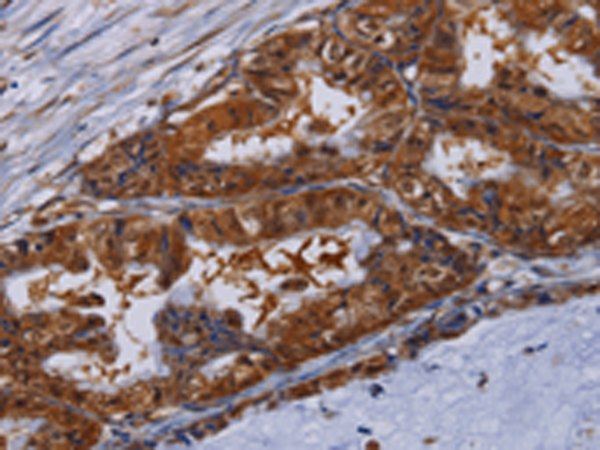

分类: 科研抗体货号: P08492别名: CT1.10; MAGE10应用: WB,IHC反应种属: Human